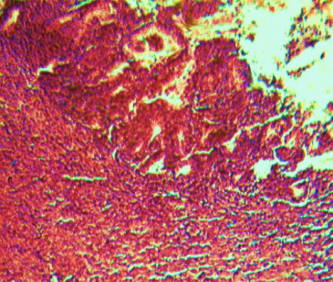

Histological evaluation of gastric lesion

Histological observation showed extensive damage of the gastric mucosa in the ulcer negative control group with necrotic lesions penetrating deeply into the mucosa accompanied by extensive edema and leucocyte infiltration of the submucosal layer (group 2).

Rats that received treatment with aqueous and methanol extracts of the leaves of D. thollonii had comparatively better protection of the gastric mucosa as seen by the reduction of ulcer area, reduced submucosal edema and leucocytes infiltration after 14 days of treatment (fig. 4).

Fig. 4: Histological study of acetic acid-induced gastric damage in rats

In fig. 4: (a’): histological section of a normal control rat: no injuries to the gastric mucosa are seen and the gastric wall is normal. ((b’): histological section of an ulcer negative control rat: there is severe destruction of the surface epithelium and necrotic lesions penetrating deeply into mucosa and submucosa layer. (c’): histological section of rats treated with Maalox (50 mg/kg): the gastric wall appears normally, but there is edema of mucosa and sub mucosa layer.(d’): the histological section of rats treated with Ranitidine (50 mg/kg): the gastric wall appears normally with all layers. (e’): the histological section of rats treated with 125 mg/kg of aqueous extract: there is mild disruption of the sub mucosal layer. (f’): histological section of rats treated with 250 mg/kg aqueous extract: there is moderate disruption of the surface epithelium. (g’): histological section of rats treated with 500 mg/kg of aqueous extract: there is mild disruption of the sub mucosal layer and edema of the muscle. (h’): histological section of rats treated with 125 mg/kg of methanol extracts: there is mild disruption of the epithelium surface and the sub mucosal layer and edema of the serosal layer. (i’): histological section of rats treated with 250 mg/kg of methanol extract: there is mild disruption of the epithelium surface and edema of the submucosal and serosal layers. (j’): histological section of rats treated with 500 mg/kg of methanol extract: there is moderate disruption of the epithelial surface although the gastric wall appears normally.